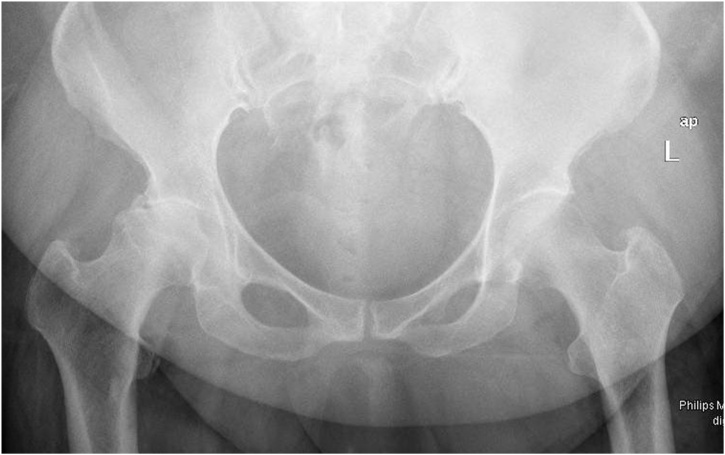

Case 2. A 47-year-old female who is a known case of psoriasis complained of right hip worsening pain and difficulty in performing daily life activities. She is known to have right hip osteoarthritis (Fig. 5), which failed conservative measures such as non-steroidal anti-inflammatories, and physical therapy. No past surgical history, however, she has a past medical history of coronary artery disease, morbid obesity and modulating immunotherapy for psoriasis. No relevant family history, and no alcohol intake or smoking.

Fig. 5.

Case 2; Anteroposterior pelvis radiograph demonstrating right hip osteoarthritis.